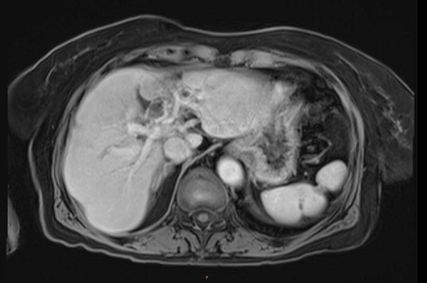

Die initiale CT zeigte eine bis zu 6cm große Raumforderung, ausgehend von der Hepatikusgabel, mit zentraler Infiltration des Leberparenchyms, suspekten Lymphknoten im Leberhilus und retroperitoneal, deutlich dilatierten intrahepatischen Gallengängen sowie Umscheidung und Infiltration des linken Pfortaderastes, jedoch ohne Thrombose. Der Befund war hochverdächtig auf einen cholangiozellulären Tumor. Die histologische Aufarbeitung einer Punktionsbiopsie ergab jedoch ein gering differenziertes, hiläres hepatozelluläres Karzinom (WHO 2019: G3). Angesichts des bildgebenden Befundes und des ebenfalls erhöhten Ca19-9 stand der Verdacht auf einen Mischtumor im Raum.

In der durchgeführten Staging-CT zeigte sich ein partielles Ansprechen (PR) mit Tumorgrößenreduktion von 49mm auf 33mm, die Lymphknoten blieben unverändert. Die Tumormarker sanken (AFP: 150, Ca19-9: 65). Aufgrund der persistierenden Diarrhö und des Verdachts auf einen Mischtumor erfolgte eine Umstellung der Therapie auf Cisplatin/Gemcitabin/Bevacizumab, wobei Gemcitabin ab Zyklus 2 wegen Fatigue auf 75% reduziert wurde und Cisplatin ab Zyklus 3 aufgrund von Ototoxizität abgesetzt werden musste. Nach vier Zyklen zeigte die MRT ein weiteres partielles Ansprechen (19×21mm), die Lymphknoten waren unverändert, die Tumormarker normalisierten sich erstmals.

Im weiteren Verlauf traten rezente embolische, bihemisphärische Infarkte auf, ätiologisch als kardioembolisch bewertet. In der letzten MRT, viereinhalb Jahre nach Erstdiagnose, zeigten sich postradiogene Parenchymveränderungen, jedoch kein Hinweis auf ein Lokalrezidiv.

Bildgebend können sich Mischtumoren wie ein HCC-iCCA-Gemisch imponierend darstellen, wie ein typisches HCC oder aber ein typisches iCCA aussehen oder sich unspezifisch darstellen. Bildgebende Hinweise auf Mischtumoren bestehen bei verschiedenartigem Kontrastmittelverhalten innerhalb eines Tumors (im Verlauf zunehmende Anreicherung, Anreicherung mit Wash-out, Anreicherung ohne Wash-out oder Hypovaskularisierung), vaskulärer Invasion und Gallengangsbeziehungen. Die Kombination erhöhter Tumormarker (AFP und Ca19-9) kann einen Hinweis liefern, ist aber nicht beweisend.